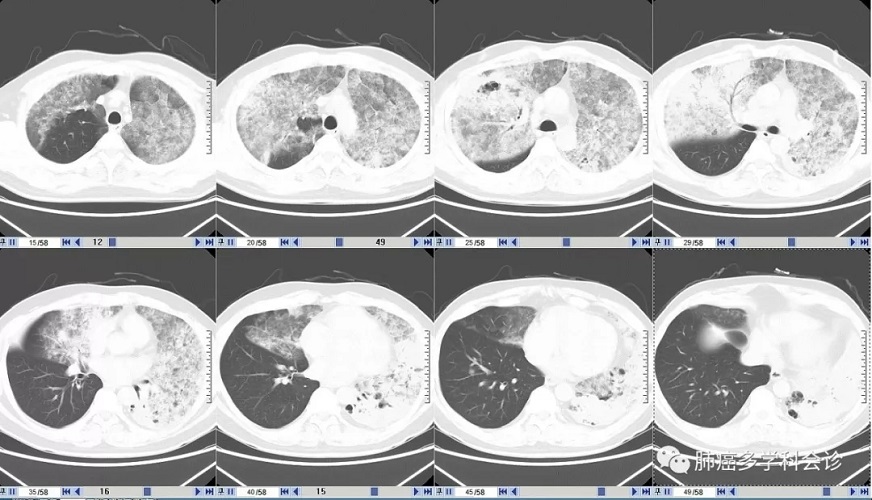

患者DHJI,男,55岁。4年前无明显诱因出现咳嗽,咳大量稀薄的白粘痰(每天咳痰约100-150ml),活动后气短,安静时呼吸平稳。

曾在省人民医院做无痛电子气管镜活检,病理:(左肺)考虑腺癌(相当原肺泡细胞癌粘液样改变),建议穿刺活检。患者拒绝肺穿刺活检。在此之后未接受任何进一步检查,也未接受任何抗肿瘤治疗。

这种 CT影像符合过去的“肺泡细胞癌”特征,大量白色稀薄泡沫痰也是其特征之一,最初的病理也考虑这一诊断。但再次活检的病理诊断:粘液腺癌,并发生了 K-ras基因突变。

患者周围血白细胞、CRP和降钙素原都不高,也没有发热,与几年前肺部CT影像特征较一致,只是肿瘤组织占领的范围明显扩大,能够排除肺部感染。临床上需要与肺部的特殊感染做鉴别。